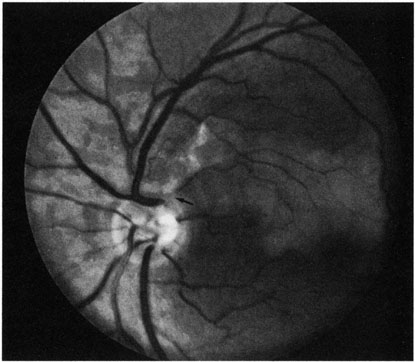

CAROTID ARTERY DISEASE The principal cause of chronic arterial obstruction is usually some kind of carotid artery disease. Atherosclerosis is the most common cause of carotid artery disease in the United States but there are other causes, such as moyamoya disease,148 fibromuscular dysplasia,149 and irradiation.150 Atherosclerosis is a disease affecting medium-sized arteries in humans. The primary symptoms of carotid artery disease are caused by the atheromatous or fibromuscular plaque.151,152 Atherosclerosis may result in narrowing (obstruction) or occlusion of the artery or in embolization. The bifurcation of the common carotid artery into the external and internal carotid artery is one of the sites at particular risk for atheromatous disease.153 The eye is frequently involved in atheromatous disease of the carotid artery bifurcation because the ophthalmic artery is one of the first branches of the internal carotid artery in the neck. Carotid artery disease can be manifest by a variety of ocular and non ocular symptoms. The ocular manifestations are important—not only because they occur in many patients with carotid insufficiency154 but also because they often are the first indication that carotid artery disease exists. There are many ways that patients with carotid artery disease present to the ophthalmologist.8 Some present with a TIA. If the TIA involves the carotid system, the symptoms include hemiparesis, hemisensory loss, aphasia, and transient monocular blindness (amaurosis fugax).155 Another group of patients have symptoms that are purely ocular. These patients present with one of several symptoms, such as (i) partial or complete visual loss due to an artery obstruction, (ii) decreased visual acuity, or (iii) pain resulting from the ocular ischemic syndrome. Other patients are asymptomatic and any ocular findings consistent with carotid artery disease are incidental. Amaurosis Fugax The type of TIA known as amaurosis fugax is the most common symptom of carotid artery disease.154,156 Amaurosis fugax is characterized by a sudden, painless, monocular loss of vision that typically lasts between 2 and 10 minutes. The patient frequently describes his or her vision as being “dark” or “dim.” The return of vision can be sectorial or altitudinal and is occasionally described as a “curtain rising.” Generally, the vision returns to normal immediately after an attack. The frequency of these attacks varies from 1 or 2 attacks per month to 10 or 20 per day. The retina—if observed during an amaurotic attack—may be normal155 or it may show obstruction (such as in central retinal artery obstruction). It may exhibit migratory white retinal emboli (within the retinal arterioles and in association with disruption of the arterial circulation)157 or it may show cholesterol emboli moving through the arterial system.155 It is important to recognize amaurosis fugax as a TIA because it is frequently caused by microembolization from an atheromatous ulcerative lesion in the ipsilateral extracranial carotid artery, at least in older patients.158,159 Approximately one-third of all patients with an untreated TIA can be expected to have a stroke; this rate is about four times greater than that of an age-matched population.160 It must be noted, however, that not all amaurosis fugax and other forms of TIA are caused by carotid artery disease. Other causes of amaurosis fugax include temporal arteritis,161 pseudotumor cerebri,161 migraine,161 structural cardiac defects,162 ophthalmic artery stenosis,163 ophthalmic artery aneurysms, hematology disorders,164,165 ocular hypertension,160 arterial hypotension, and vasospasm.165 A group—usually younger patients—may have no identifiable disease.161,162,167 Ocular Ischemia There are several forms of chronic arterial obstructions that occur in carotid artery disease. These typically result from hypoperfusion of the retina caused by either stenosis or the complete obstruction of either the extracranial internal or the common carotid artery. One form of chronic arterial occlusion is a unilateral retinopathy that is ipsilateral to the carotid artery lesion and is characterized by cotton-wool patches, dilated arterioles and veins, an absence of hemorrhages, and normal vision. This retinopathy was first recognized as a sign of carotid artery disease by Hollenhorst154 in 1958, although such changes had been previously noted after ligation of the common and external carotid arteries in the treatment of traumatic carotid cavernous fistula.168 In a milder form of this retinopathy, the only abnormality may be larger retinal arterioles on the side of a ligated carotid artery in patients with hypertension169 or asymmetric hypertensive retinal vascular changes, in which the eye ipsilateral to the carotid lesion has the fewer changes.8 Another type of chronic ophthalmic artery obstruction produced by hypoperfusion caused by stenosis or occlusion of the ipsilateral extracranial carotid artery was first reported by Hedges170 and termed venous stasis retinopathy by Kearns and Hollenhorst.171 Venous stasis retinopathy is probably not a good term for this condition, however, because the basic mechanism involves reduction of the arterial inflow, not the venous outflow. Even more confusion has resulted from the use of the term to describe the features of the nonischemic form of central retinal vein obstruction.172 A better term is hypoperfusion or hypotensive retinopathy.172 Klijin and co-workers414 found this type of chronic ocular ischemia in approximately one-third of patients studied with symptomatic carotid artery occlusive disease. Hypoperfusion retinopathy is characterized by dot and blot hemorrhages in the midperiphery of the fundus, by venous tortuosity and engorgement, by microaneurysms, and by the occasional sludging of blood within the veins. Fluorescein angiography may show areas of capillary nonperfusion; it may also show microaneurysms in the midperiphery and slow arm to retina or arteriovenous transit time (Fig. 9A and 9B).174 The condition does not usually affect the posterior pole, and patients typically have normal visual acuity, although an occasional patient may have macular edema.174 The entire periphery of the eye is usually affected, although there may be more hemorrhages in one quadrant than another. Patients occasionally experience ocular discomfort or eye pain despite normal intraocular pressure. Reduction of the ophthalmic arterial pressure is a pathognomonic feature. Disc edema and disc collaterals are generally not present. The electroretinogram shows abnormalities in both the a- and b-waves (see Fig. 9C).